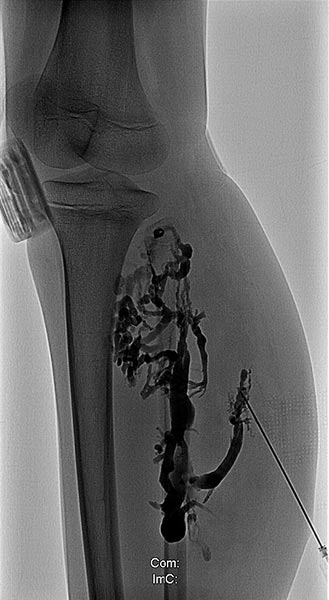

Phlebography after direct puncture of the venous malformation shows a large-lumen drainage vein communicating with the popliteal vein in the popliteal fossa. This must be occluded before sclerotherapy, otherwise the sclerosing agent could unintentionally dislocate through this communication and potentially cause thrombosis of the deep venous system of the leg and/or pulmonary embolism. In addition, there is an ongoing, increased risk of thromboembolism in this patient even outside of sclerotherapy, which can be significantly reduced by occlusion of the communication.

To occlude the vein, a large-lumen introducer sheath is first advanced via a guidewire. This sheath is used to insert the laser fiber and is advanced via the vein to the communication point in the popliteal fossa.

A laser fiber is advanced through this sheath for endovascular laser therapy. The heat of the laser beam causes massive irritation of the vein wall, which subsequently closes quickly. Thrombus formation immediately occurs around the laser tip.

After occlusion via laser fiber and contrast injection via the pulled-back introducer sheath, there is no more outflow of the contrast medium via the communicating vein. Thus the communication is successfully occluded. Only the venous malformation is still contrasted. This is now ready for sclerotherapy, as the sclerosing agent can no longer drain into the deep venous system of the leg.

After additional puncture of a very distal part of the large-lumen communicating vein and contrast injection, there is no more outflow into the deep venous system. Thus, even in the long term, the risk of embolism of thrombi from the venous malformation into central conducting veins is eliminated.